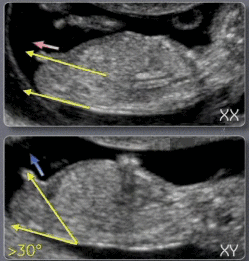

Moi là comme ça je dirai filles... L'avantage c'est que t'as pas longtemps a attendre lol.Écho ce matin donc tout va bien pour la trisomie et pour l'instant contrairement à mon fils ou des 12sa il était sur casiment que c'était un garçon la il ne se prononce pas il me dira le mois prochain il m'a dit donc je garde espoir encore pour je fillAfficher la pièce jointe 711891 Afficher la pièce jointe 711892 e lol